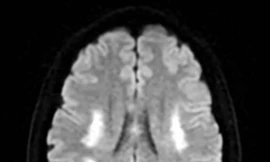

TPO - Người phụ nữ 42 tuổi, đã có hai con trai sinh thường, bất ngờ nhập viện trong tình trạng nói đớ và được chẩn đoán nhồi máu não chỉ vài ngày sau khi tiêm thuốc kích thích buồng trứng trong quy trình thụ tinh trong ống nghiệm.